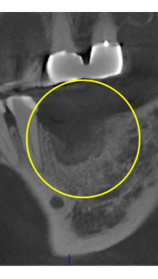

インプラント撤去

Er:YAGレーザー+コールドレーザーの例です。

Er:YAGレーザー+コールドレーザーで治療した箇所の経過です。

左の画像が照射前です。1ヶ月でここまで治癒しました。